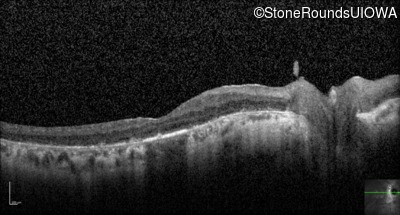

Optical Coherence Tomography - Left - 20/70 sc

Exemplar / OCT Stack

OCT Stack

Infrared Fundus Photograph - Left - 20/70 sc

Exemplar